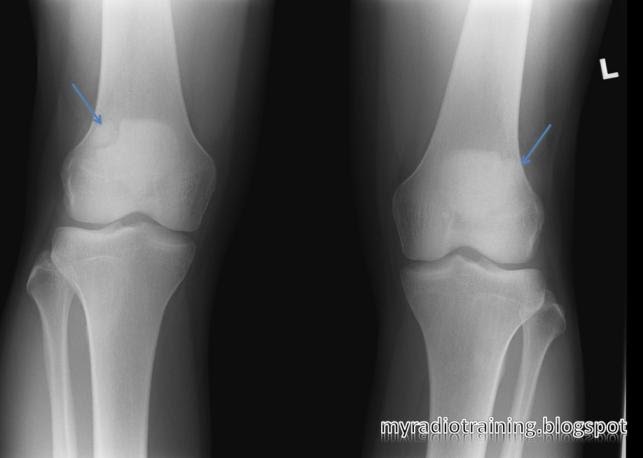

Trois types ont été décrits (Saupe) :

- Type I : le fragment est situé en bas de la patella (5% des cas),

- Type II : le fragment est situé sur la partie latérale de la patella (20% des cas),

- Type III : le fragment est situé sur la partie supérieure et latérale de la patella (75% des cas) et souvent bilatérale.